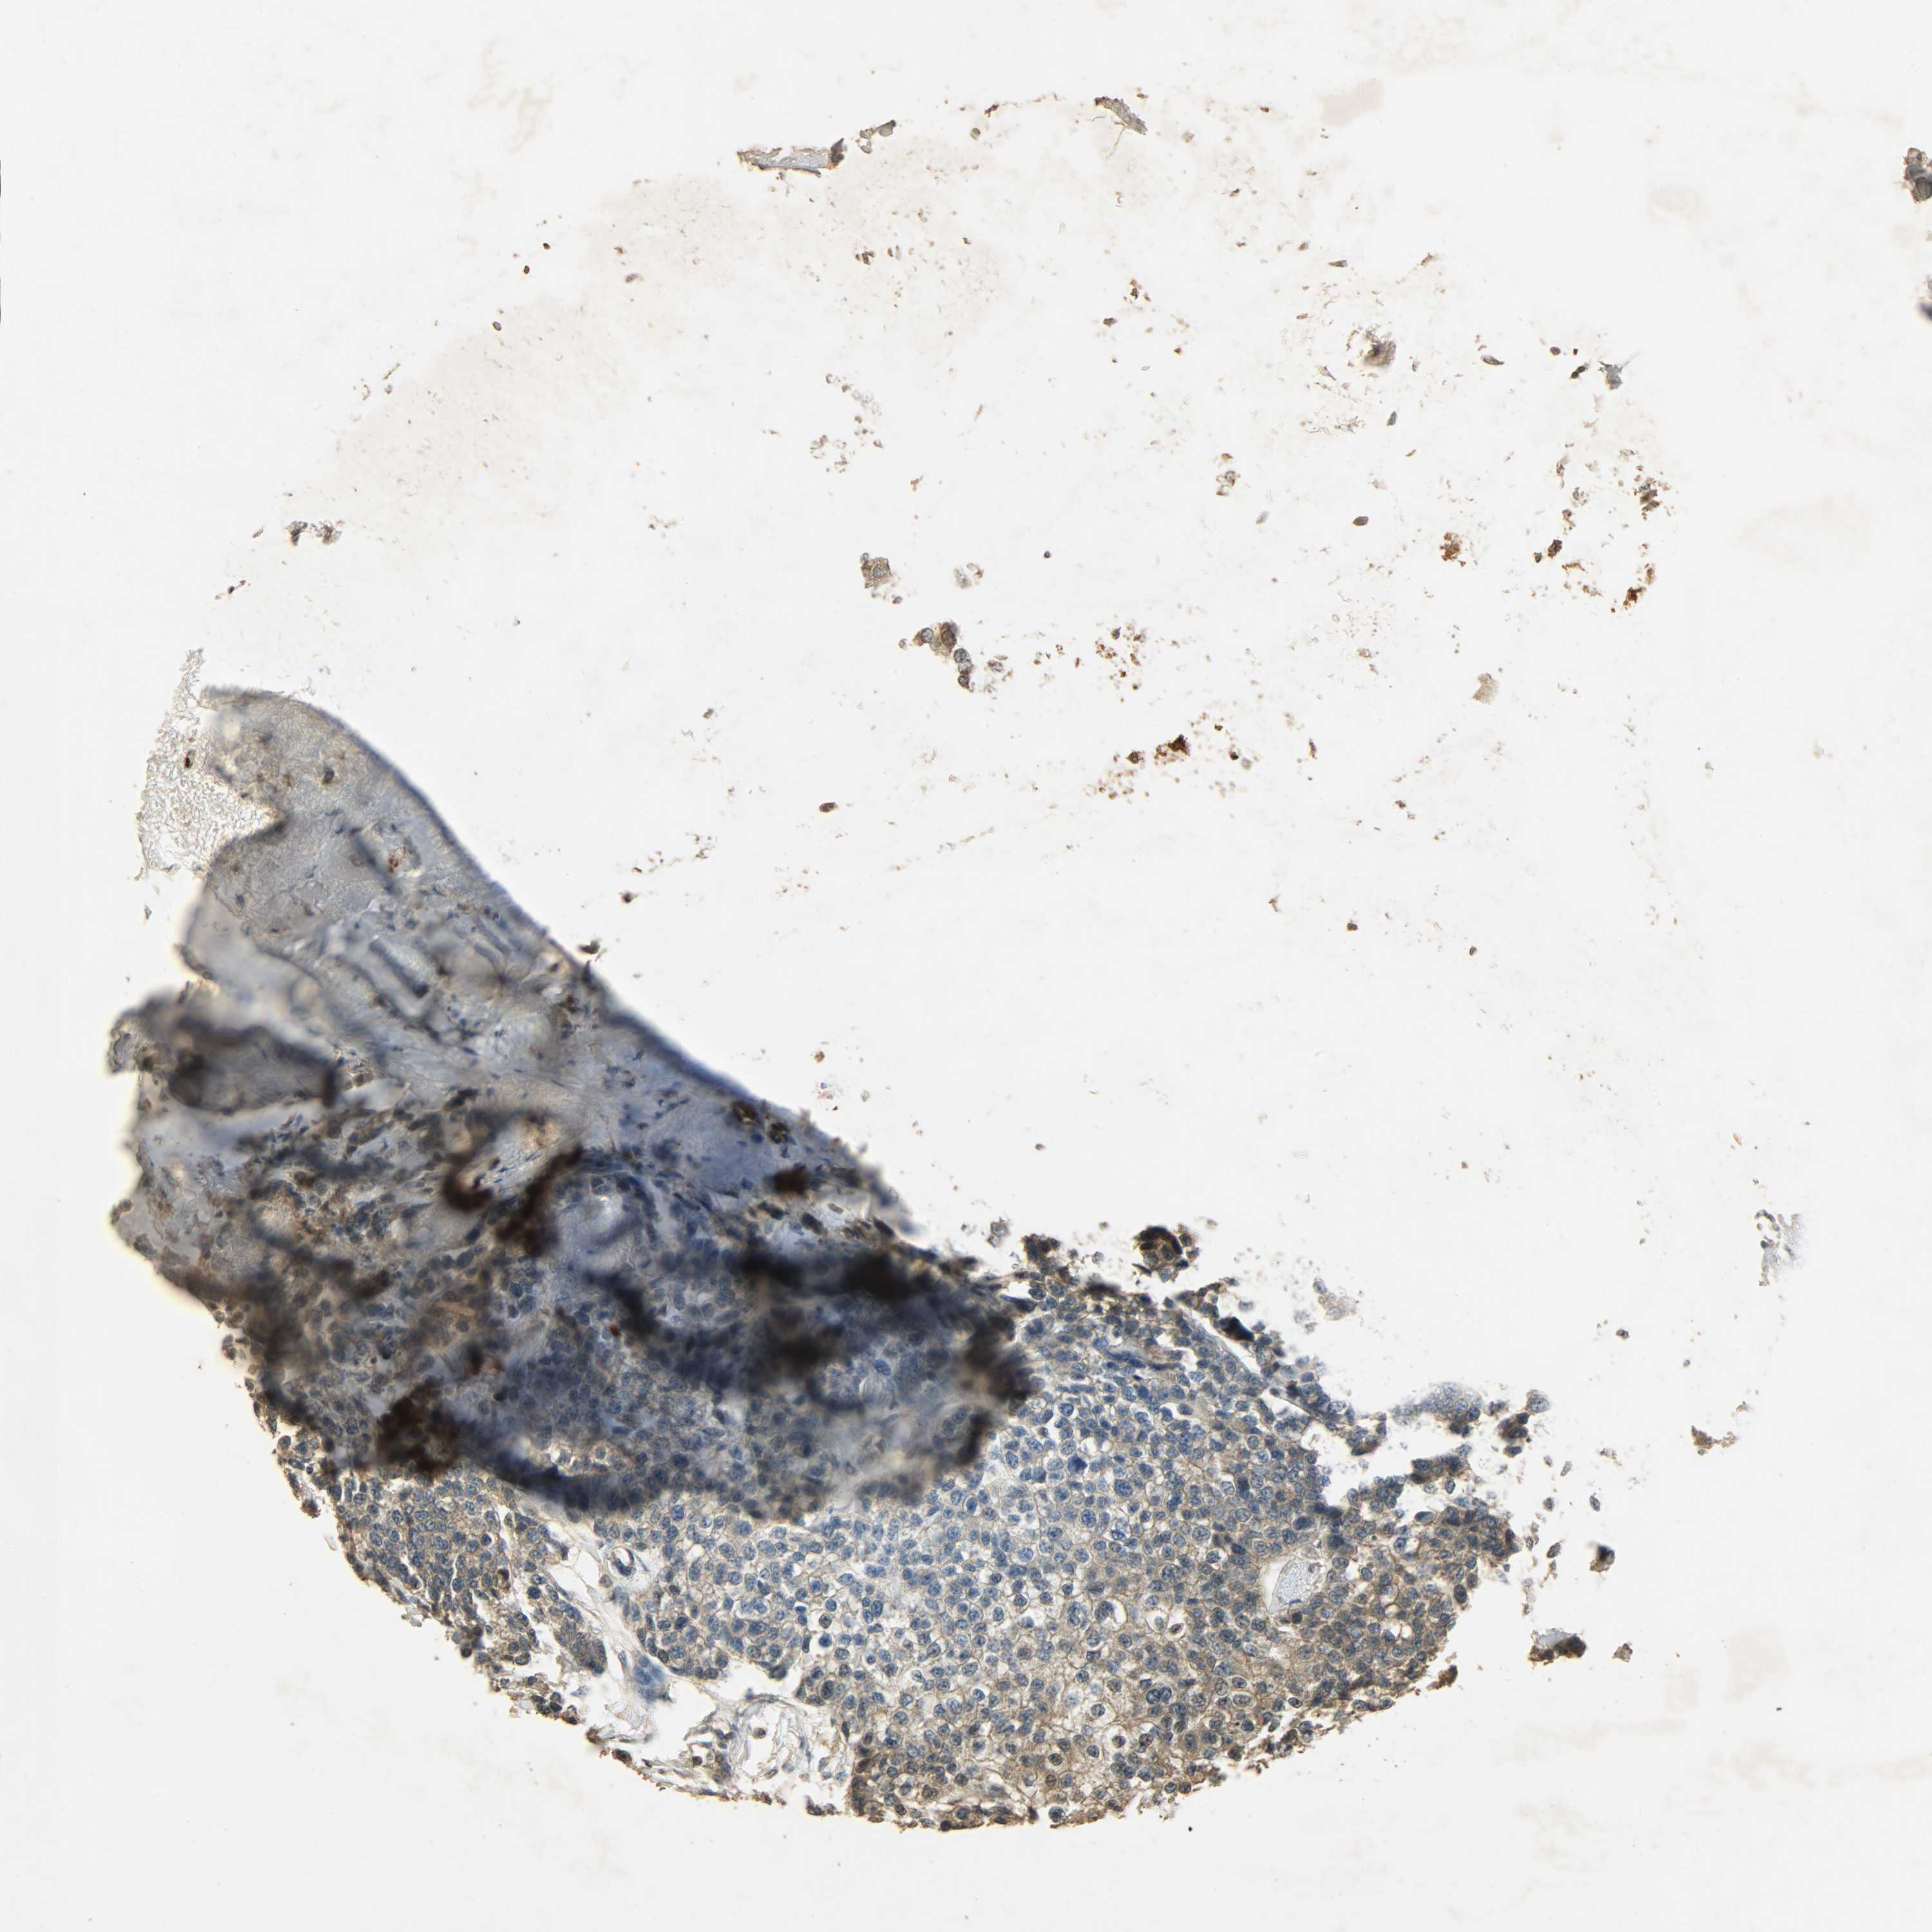

CANCER BREAST CANCER Show tissue menu

BRCA TCGA BRCA VALIDATION PROTEIN EXPRESSION